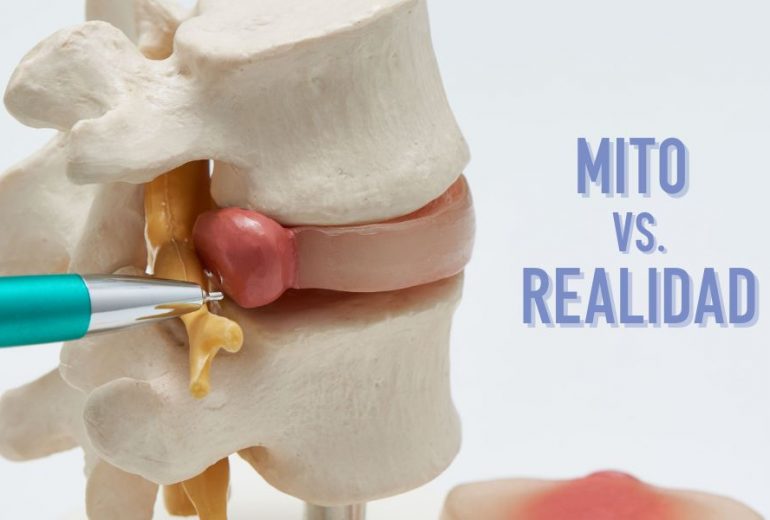

Patología Discal: Separando los Mitos de la Realidad

La hernia discal es una afección común de la columna vertebral, ocurre cuando el núcleo interno blando -conocido como núcleo pulposo- de un disco intervertebral se sale y empuja a través de una capa externa debilitada del anillo fibroso -parte externa del …